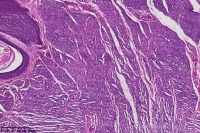

背部包块,皮内痣?

性别

女

年龄

41岁

背部包块

图2

考虑符合:皮内痣

皮内痣

皮肤皮内痣,切缘未净